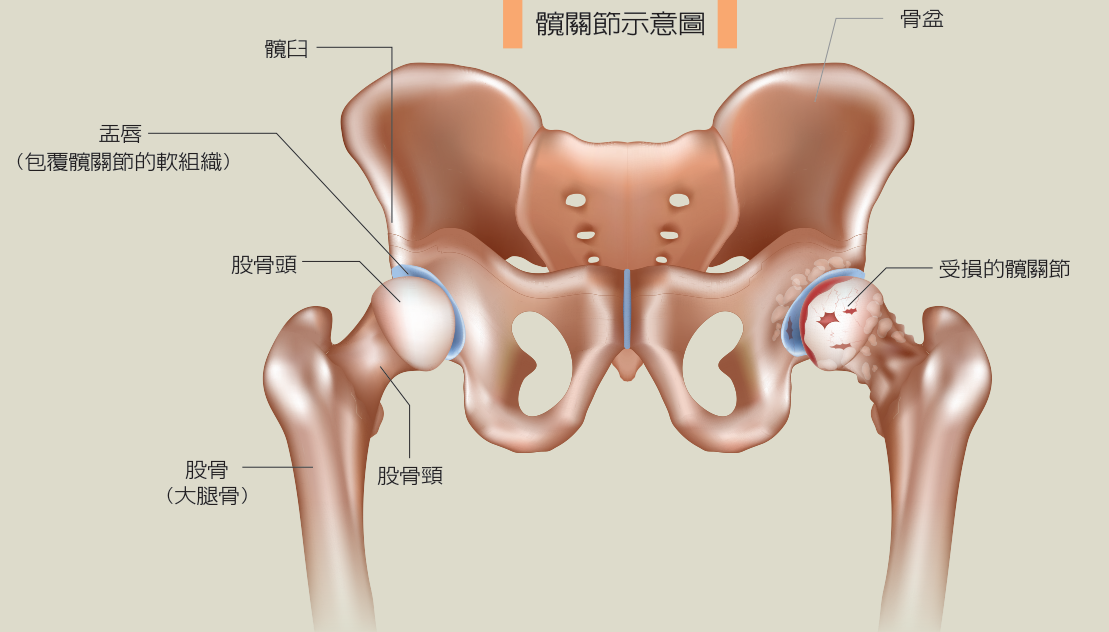

大腿疼痛跛行全髖關節置換助恢復生活品質 永越健康管理中心

阿嬤髖關節退化難走路醫師一招治療重拾走路樂趣 骨科 復健 該看哪科 元氣網

髋关节疼痛 僵硬 活动受限 髋关节骨性关节炎可以这样应对 于运动

屁股大腿痛 髖關節炎 剖析髖關節位置 原因及退化要吃什麼 Esdlife健康網購